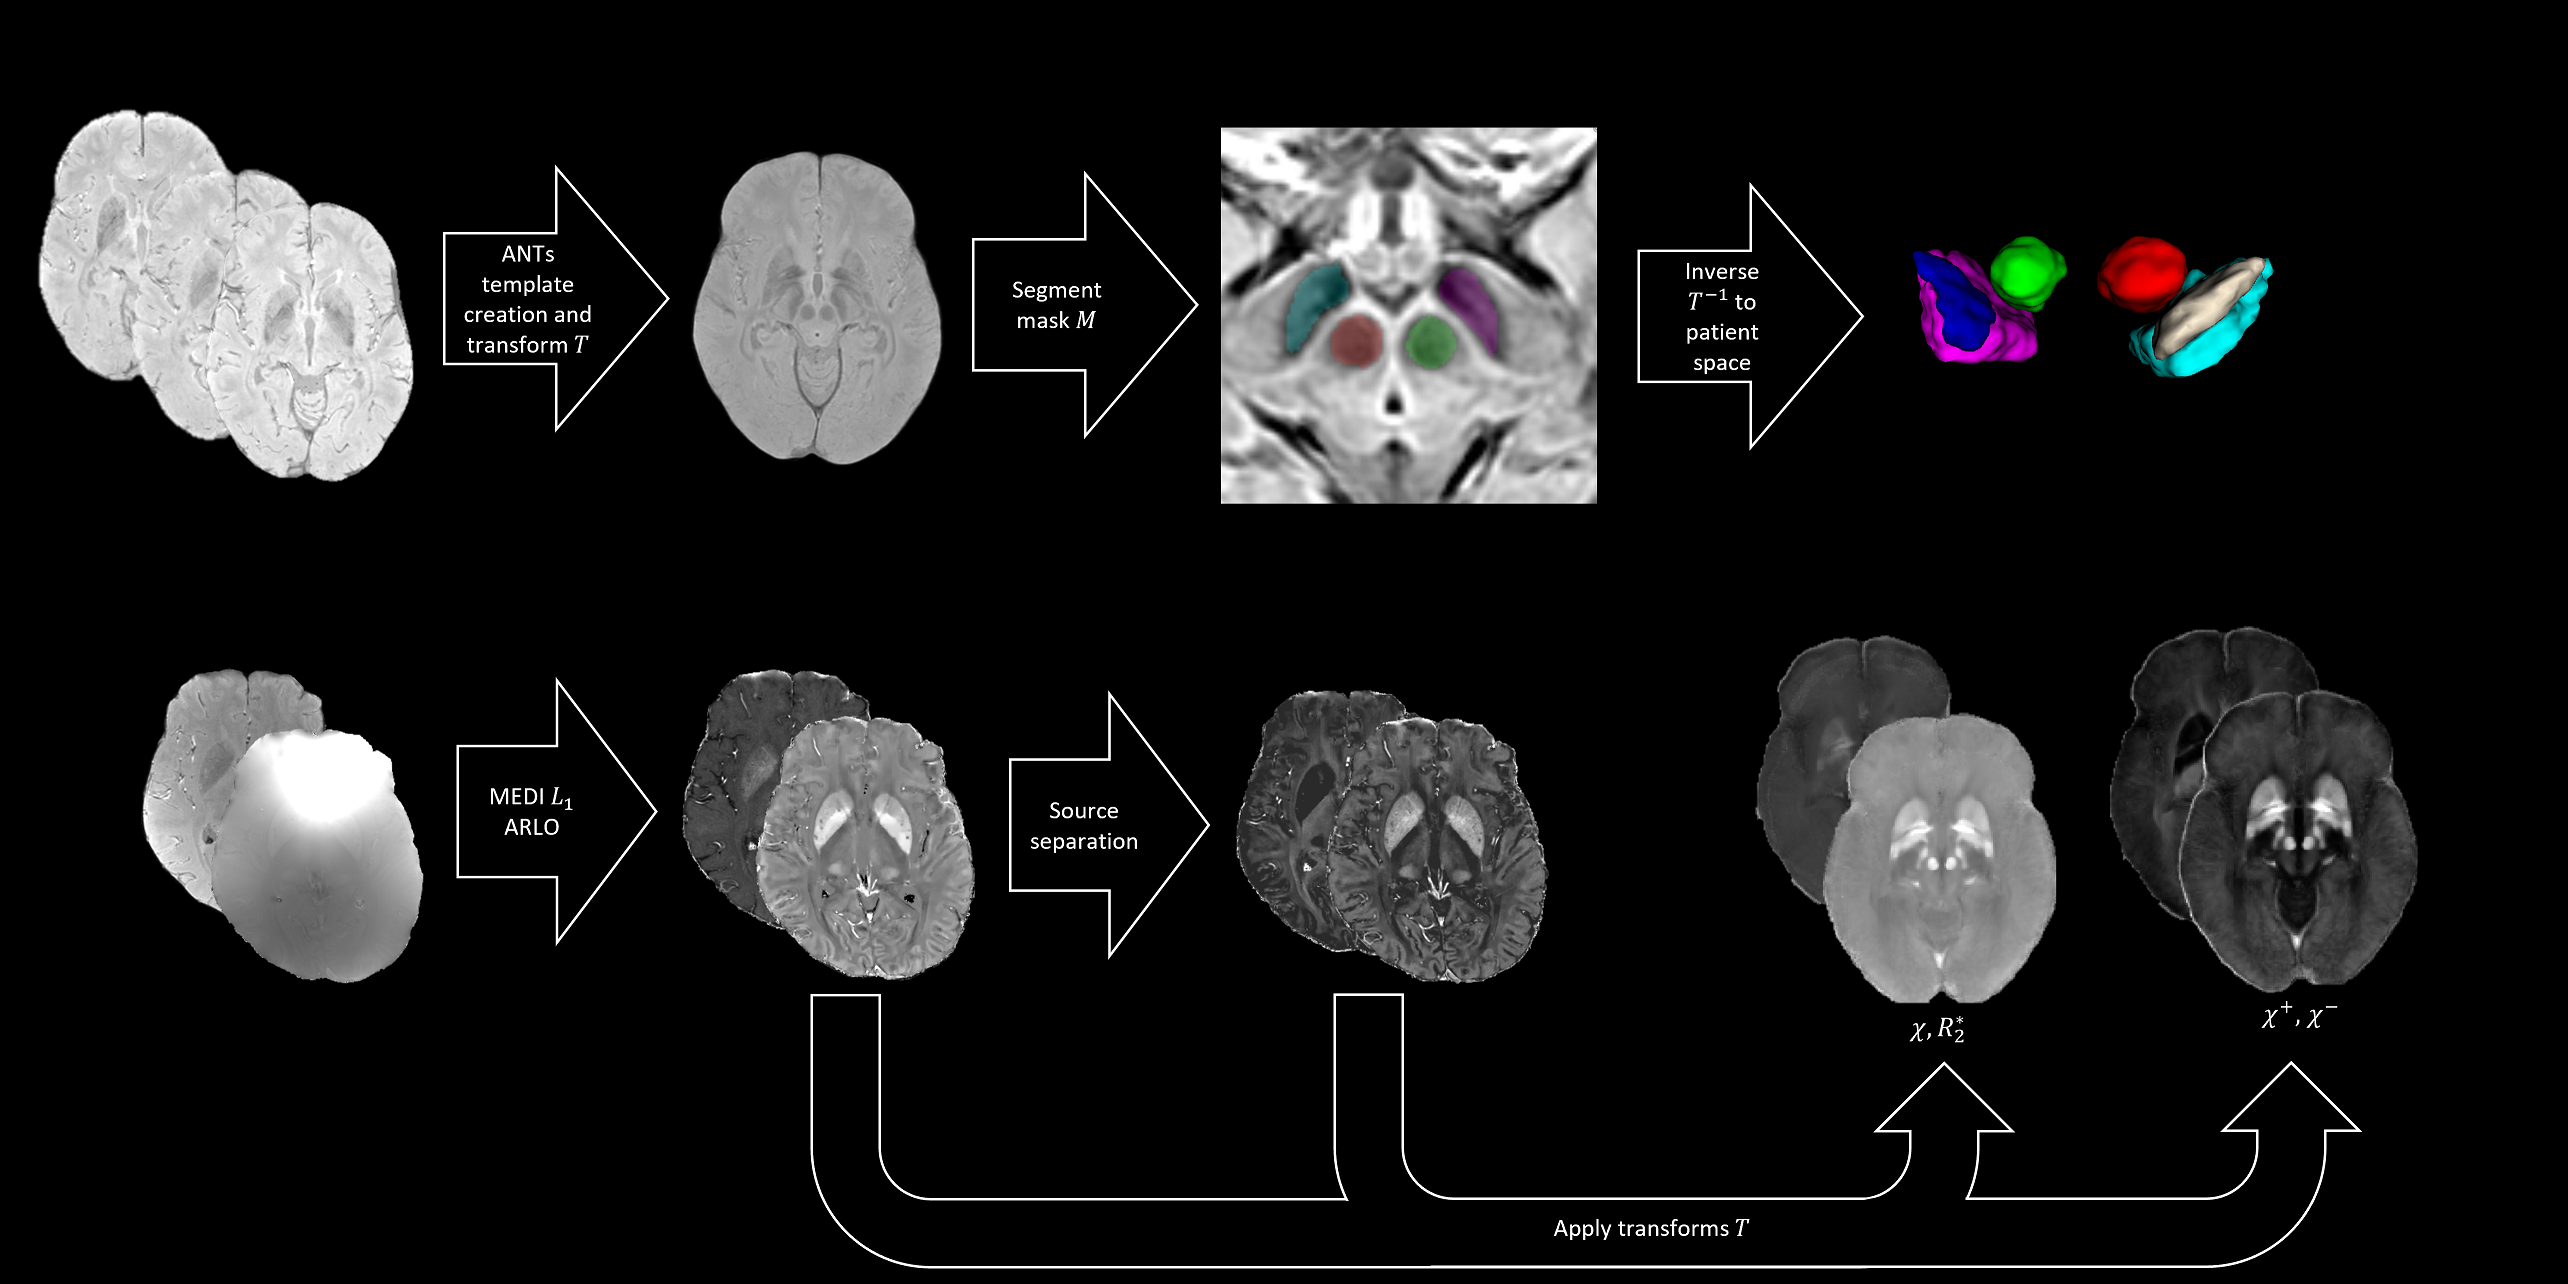

Method: QSMs acquired from a multi-echo gradient echo sequence and susceptibility15,16,17,18,19,20,21 and R2*22, source separation23 and myelin maps24 were reconstructed. The magnitude T2*w atlas was generated after bias correction25, brain extraction26, and template construction27 in Advanced Normalization Tools28 with co-registered susceptibility and relaxation atlases. Inverse transforms map segmentations to patient space [figure1].

Created template to patient space.